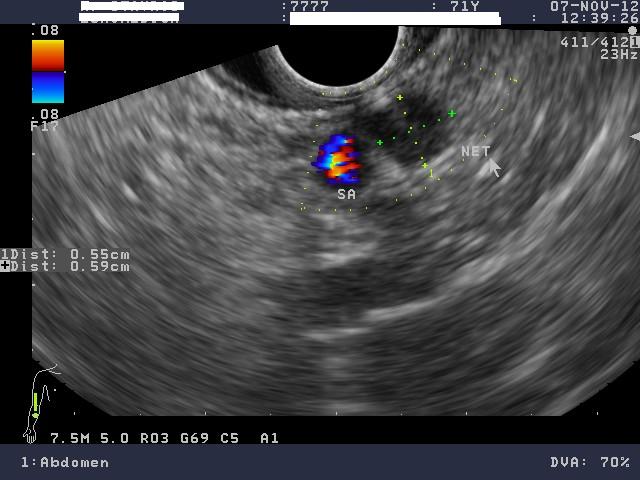

3) Νευροενδοκρινικός όγκος παγκρέατος (ινσουλίνωμα)

Άνδρας 71 ετών παρουσίαζε υποτροπιάζοντα επεισόδια υπογλυκαιμίας από 2ετίας. Είχε υποβληθεί σε λεπτομερή ορμονολογικό έλεγχο σε εξειδικευμένο ενδοκρινολογικό κέντρο που ήταν συμβατός με υπερπαραγωγή ινσουλίνης από πιθανό ινσουλίνωμα. Παρά ταύτα, ο απεικονιστικός έλεγχος με αξονική τομογραφία άνω-κάτω κοιλίας με λεπτές τομές (MDCT) και μαγνητική τομογραφία (MRI) κοιλίας δεν ανέδειξε τον όγκο. Ο ασθενής παραπέμφθηκε για έλεγχο του παγκρέατος με ενδοσκοπικό υπέρηχο (EUS). Ο ενδοσκοπικός υπέρηχος με linearενδοσκόπιο έδειξε ένα στρόγγυλο, υποηχοϊκό μόρφωμα, με ομαλή παρυφή, διαμέτρου μόλις 6 χιλιοστών στα όρια σώματος και ουράς του παγκρέατος. Δεν κρίθηκε σκόπιμο να γίνει βιοψία, αφού τα ευρήματα ήταν τυπικά ενός νευροενδοκρινικού όγκου. Το ινσουλίνωμα ήταν κοντά στην επιφάνεια του παγκρέατος και σε απόσταση από τον κυρίως παγκρεατικό πόρο. Συνεστήθη χειρουργική αφαίρεση με εκπυρήνιση του όγκου αλλά ο ασθενής προτίμησε να ακολουθήσει συντηρητική αγωγή με διαζοξίδη.